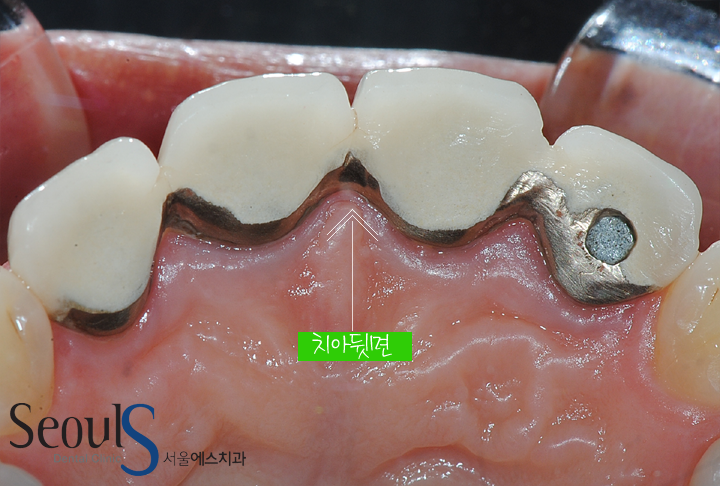

뒷면 모습입니다

치아 속은 메탈이고 겉은 치아 색인 보철물로 4개의 크라운이 묶여 있는 모습입니다

보철물 속이 메탈이기 때문에 치아색이긴 하지만 불투명한 치아 모습입니다